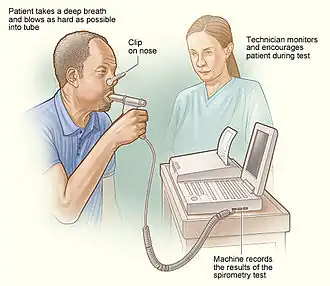

- VO2 consumption per minute using a spirometer (with the subject re-breathing air) and a CO2 absorber